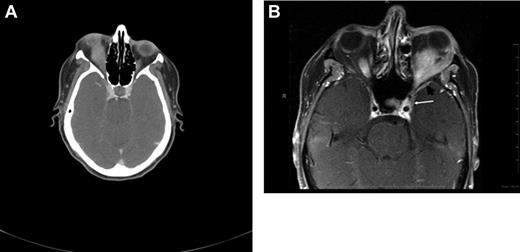

CT and magnetic resonance tomography (MRI) with contrast enhancement are the primary radiographic imaging tools in the evaluation of ocular adnexal proliferations. They aid in the assessment of location, size, and degree of infiltration; however, they cannot reliably distinguish between benign and malignant processes. Cuts of 1 to 3 mm are performed in axial and coronal planes, including the cavernous sinus and parasellar area to determine extraorbital extension. Typical imaging appearance of a lymphoid lesion is that of a unifocal, homogeneous, well-circumscribed lesion of isodensity to slight hyperdensity, with mild to moderate contrast enhancement, and smooth, distinct borders, molding into adjacent tissues and displacing rather than infiltrating orbital structures (Figure 3).55,56 Infiltration into the globe or bony erosions are unusual features of MALT lymphoma and should raise suspicion for high-grade transformation with aggressive clinical behavior.

Radiographic presentations of OAML. (A) CT image of right orbital MALT lymphoma involving the inferior rectus muscle, causing mild proptosis. (B) MRI of left orbital MALT lymphoma involving the lateral and inferior rectus muscles, causing medial deviation of the optic nerve, with involvement of the cavernous sinus (white arrow) and mild dural enhancement in the medial anterior cranial fossa (black arrow). Analysis of the cerebrospinal fluid was positive for lymphoma. This case represents an unusual extension of OAML into the central nervous system leading to lymphomatous meningitis.